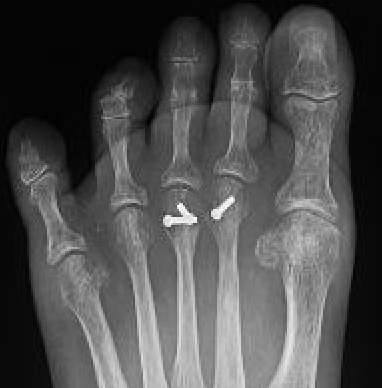

Plantar plate repair / reconstruction

Indication

MTPJ instability / subluxation / dislocation

Techniques

Direct repair to proximal phalanx

- plantar / dorsal approach

- anchors / transarticular approach

Reconstruction

Dorsal approach repair technique